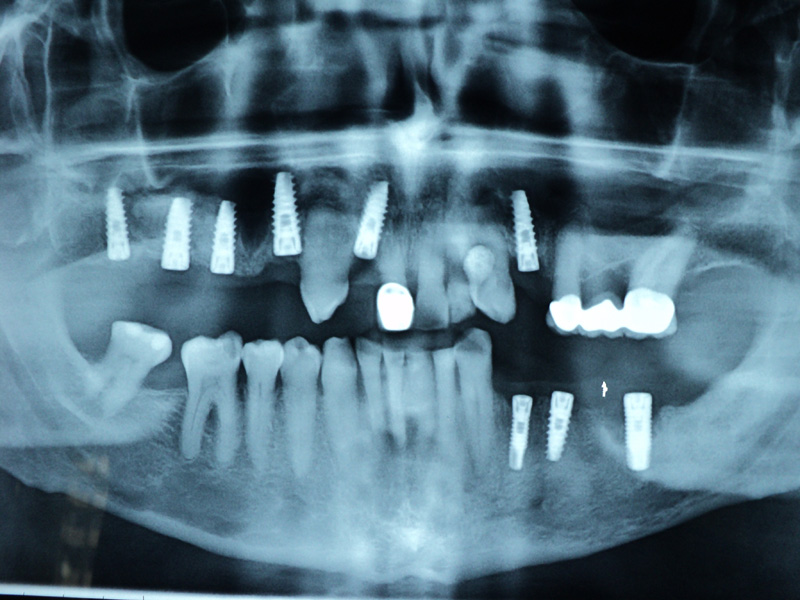

Radio-

grafii

Implante - Galerie Foto